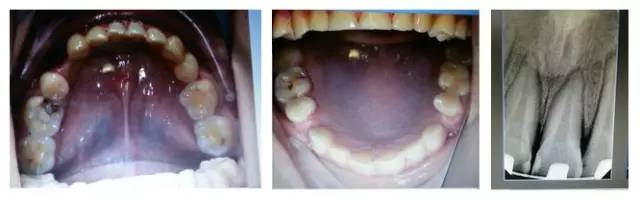

(以下為治療后的照片:患者癥狀得到了良好改善。)

6.jpg

足以看出,尖牙保護(牙合)在臨床工作中的重要作用,它是以尖牙為支撐,對其他牙齒起到保護作用。其特點是正中關系(牙合)與正中(牙合)協(xié)調(diào);側方咬合運動時,工作側只有尖牙保持接觸非工作側牙齒不接觸;在作前伸咬合運動時,上下頜前牙切緣相對接觸,后牙不接觸。尖牙具有適合制導的舌面形態(tài),可使用(牙合)力趨于軸向;牙根長且粗大,支持力強;尖牙位居牙弓前部,在咀嚼時構成第Ⅲ類杠桿,能抵御較大的咀嚼力;以及尖牙牙周膜感受器豐富,對刺激敏感,能及時調(diào)整反應都是尖牙的有利條件。尖牙形態(tài)的恢復在此例正畸治療中,對前牙、后牙都起到了很好的保護作用,也能保證后期按照標準(牙合)進行(牙合)重建時后牙無干擾。功能在先,美觀在后,權老師為您展示了這樣的治療理念。

要想成為一個合格的(牙合)學醫(yī)生,僅僅局限于處理患者已經(jīng)出現(xiàn)的問題是遠遠不夠的,善于挖掘患者潛在隱患的醫(yī)生才是合格的,細致入微的權老師還在病例中發(fā)現(xiàn)兩個潛在問題,群里的同仁們,來吧,跟著權老師,看圖說問題。

7.jpg